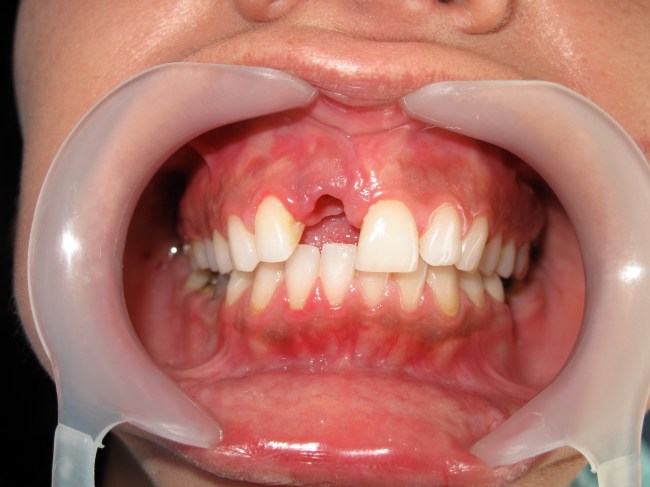

Dental implants are most difficult in the esthetic zone especially when it needs Bone graft management.